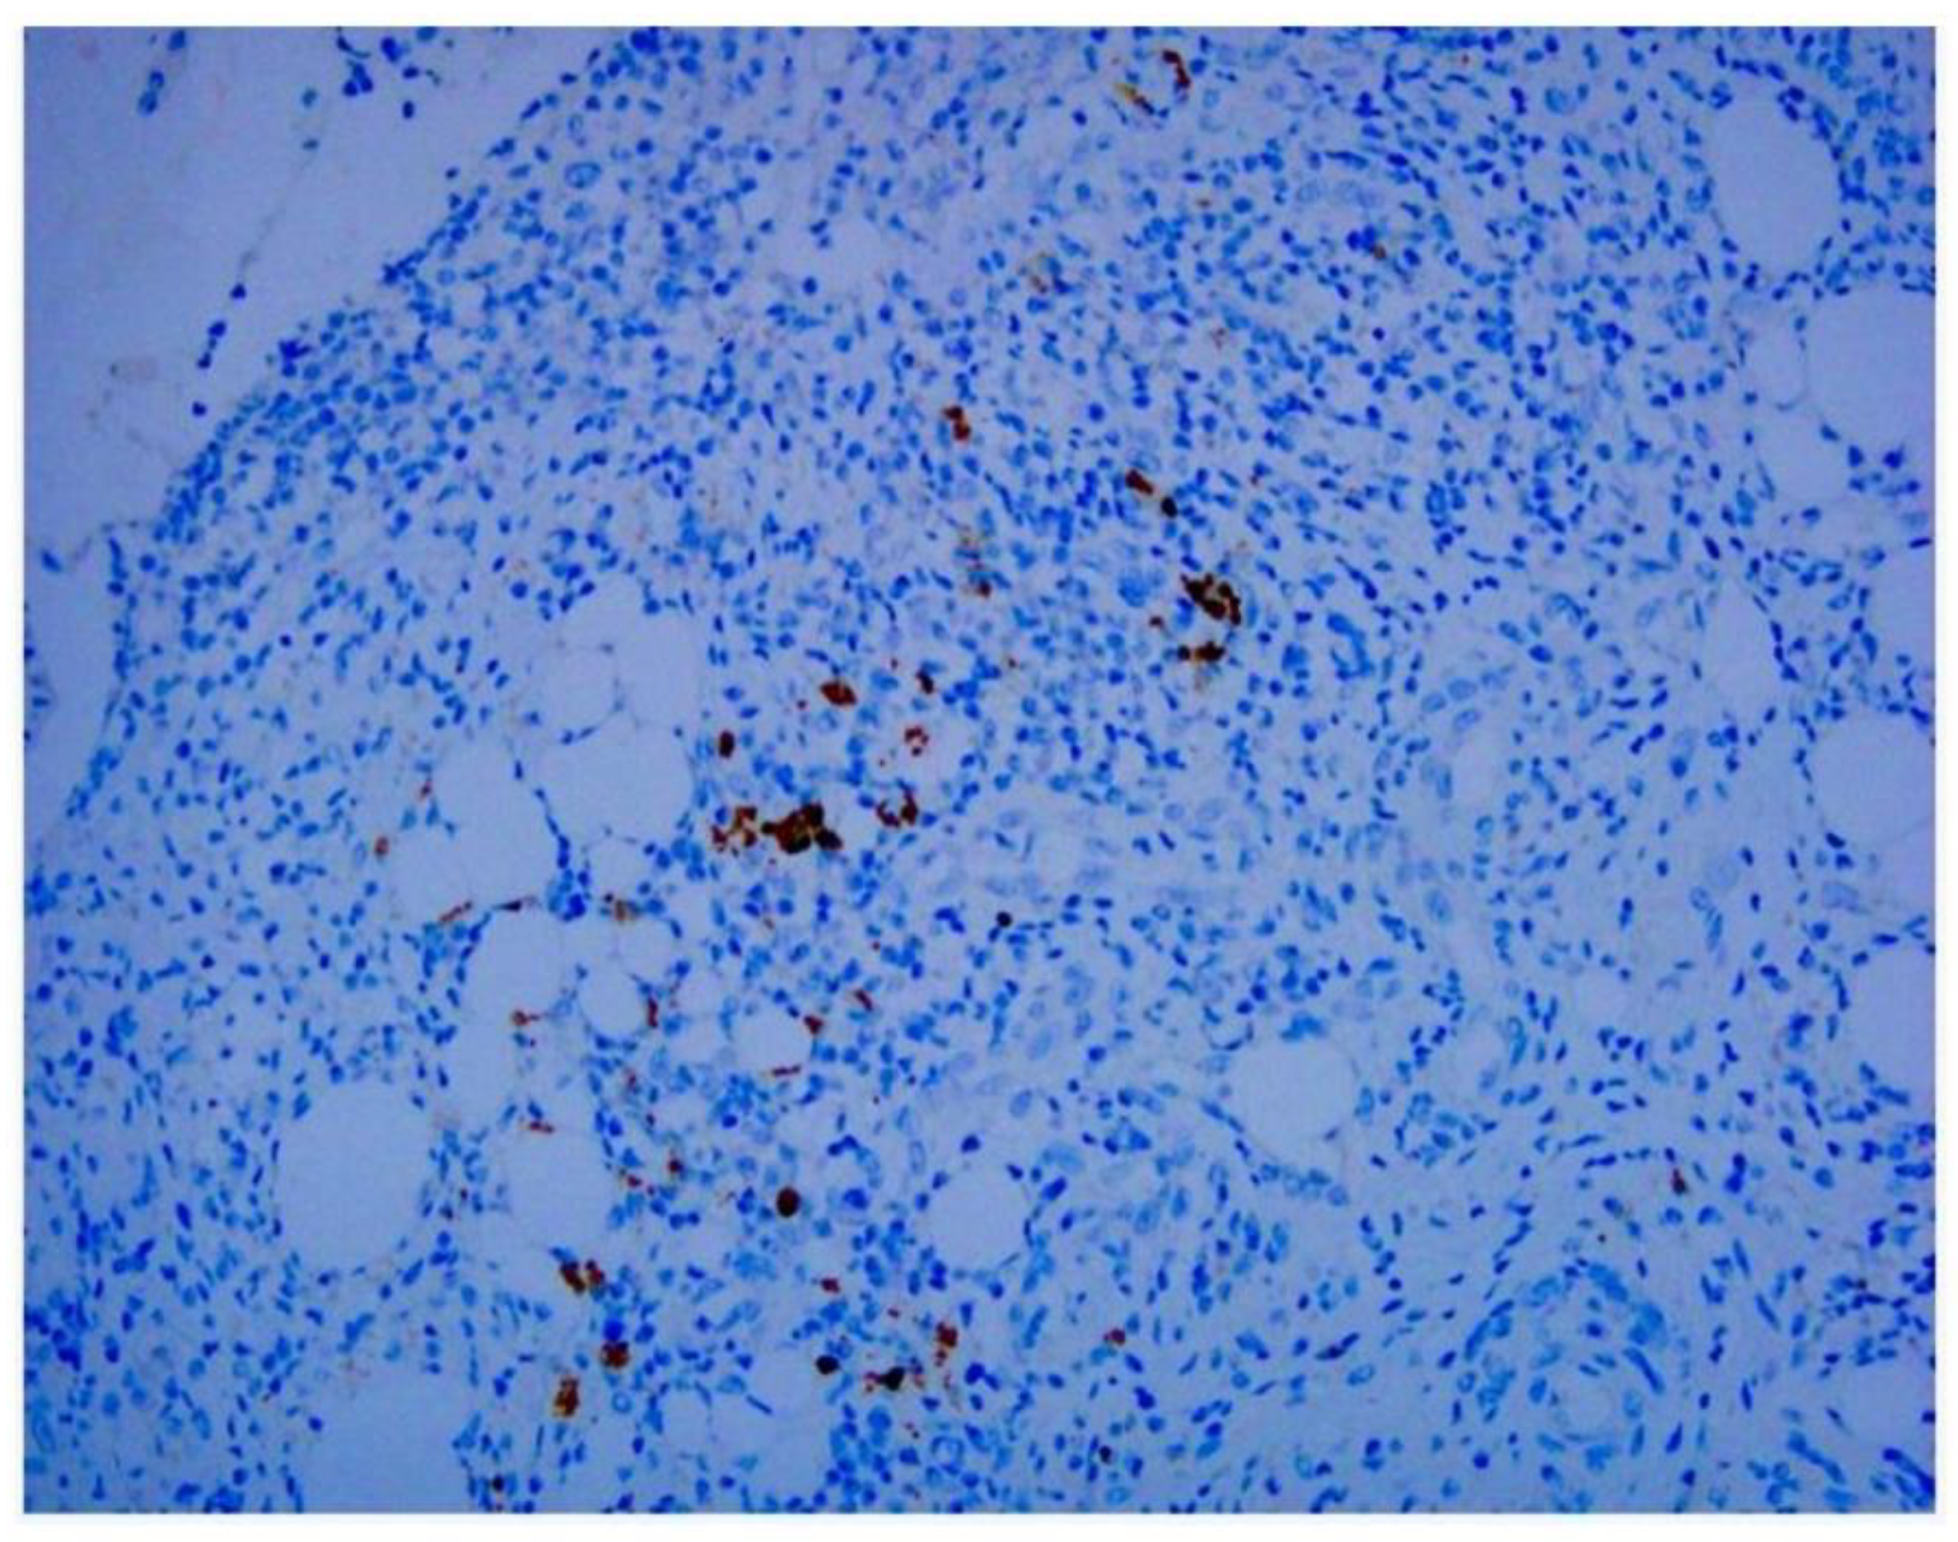

Adenovirus immunohistochemical staining was observed in the cytoplasm and nuclei of epithelial cells and monocytes in some patients (Figure 1, Figure 2 and Figure 3).

Histopathological characteristics observed in routine H&E staining studies cannot be used to differentiate adenoviral infection from other causes of appendicitis, but H&E staining is often used to predict treatment response, diagnose cancer, and determine the likely outcome of the disease [21]. Our study revealed approximately the same proportion of stained cells. Identification of adenoviral inclusions by H&E staining is not very accurate because autolyzed and/or necrotic cells and poorly fixed tissue samples may produce artifacts from similarly stained cells. We found that IHC analysis more easily visualized virus-infected cells than H&E staining. We noted that, in addition to mononuclear inflammatory cells and dendritic cells in follicles beneath the lamina propria, adenoviral antigens were also found in epithelial cells (Figure 1, Figure 2 and Figure 3). In addition to being used to detect pathogen antigens in fixed tissue, IHC using monoclonal and multiclonal antibodies can complement fresh tissue PCR and culture for the direct diagnosis of infectious diseases [22].When diagnosing adenovirus infection, various types of samples can be used, including nasopharyngeal aspirates and swabs. These samples can then be analyzed using a variety of methods, with PCR being considered the “gold standard.” Many commercial PCR kits have been developed by laboratories around the world. These kits can be used to detect adenovirus in a variety of samples [23]. Different multiplex PCR combinations can target most, if not all, known infectious pathogens affecting the human respiratory system. PCR is also widely used to detect adenovirus infection. Molecular testing detects a wide range of enteric pathogens and has low discriminatory accuracy in distinguishing symptomatic from asymptomatic individuals. Even so, multiplex PCR allows for direct comparisons between different countries and reveals considerable environmental specificity [24].

Figure 1. An immunohistochemical assay using anti-adenovirus antibody shows epithelial cell staining with viral inclusions suggestive of adenovirus in the cytoplasm (original magnification ×200).